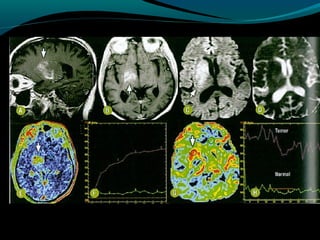

Glioblastoma

Maligno;

Origem astrocítica;

Grau IV;

60% dos astrocitomas;

15% das neoplasias intracranianas;

Mais frequente em adultos;

Sobrevida de 9 a 12 meses;

TC:

Geralmente supratentorial;

Infiltra substância branca;

Processo expansivo iso ou hipodenso de limites mal

definidos e necrose central;

Pode apresentar hemorragias;

Calcificações são raras;

RM:

Sinal heterogêneo em T1, T2 e FLAIR; (necrose, cistos,

hemorragia, neovascularização); mas predomina

hipointensidade em T1 e hiper em T2 e FLAIR;

Realce difuso e heterogêneo pelo Gd;

Redução do NAA

Aumento do Co

Redução da razão Mi/Cr

Picos de lipídeos e lactato

Centro necrótico não restringe à difusão;

Na perfusão: aumento do CRBv máximo;

OBS: capacidade invasiva impede ressecabilidade total;